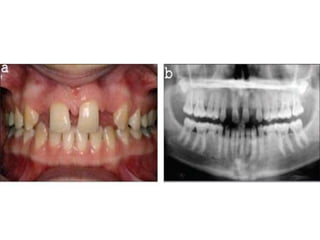

2. Missing Teeth

• Hypodontia

• Oligodontia

• Anodontia